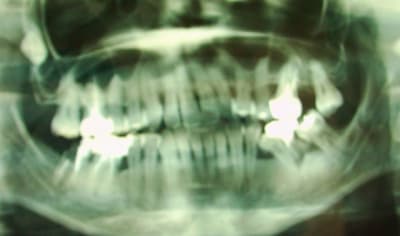

bonjour je voulais avoir votre avis pour la 35, est que je l'enlève de suite ou est qu'on peut en faire quelque chose?

Oui, alhoun mais la 37 qui a subi aussi une sacrée version mésiale te ferait a mon avis transpirer pas mal pour l'axe implantaire 36

Et dans le cas du bridge 5,7 , on a peu de hauteur pour l'intermédiaire . Et le redressement de 35 :ouahouh?!!!, de l'abnégation de la part de l'ortho (37 tres peu ancrée en son os alvéolaire).

Ce qui est dit. Donc, désolé , mon alhoun, l'extraction de 35 risque d'etre votée @++++

A choisir, si une dent est à extraire ce n'est certainement pas la 35 qui est saine alors que la 36 est nase, franchement la 35 peut revenir avec l'ortho fonctionnelle.

Justement je voulais lui faire de l'ortho fonctionelle, mais j'ai des doutes quand au résultat.

Mac, je t'envoie un napoleon si tu arrives a (faire) redresser cette 5 par fonctionnel ou meme par mini implant. Il faudra une version distale, certes et aussi une gression linguale avec sans doute a la clef un diasteme de 2 a 3 mm entre 4 et 5.

1) paro !!!

2) révisions endo !!!!!!!!!!!

3) ortho avec surélévation concommitante

(la 36 sera extraite mais quid de l'os alvéolaire en distal de 35 ?)

36 à faire sauter c'est sûr.

Ensuite tu peux tenter SB mais ce sera long si on rajoute le probléme de 37 versée et 24/25 égressées.

Possible faire piste ou plaque avec verin entre 34/35 pour redresser 35. Voir quel plan occlusal choisir pour permettre alignement horizontal et/ou prévoir tailler/dépulper 37, 25....

avulsion 36 redresser 35 qui va se retrouver en 36 soins multiples et prothese ou implant 34

Je dirai comme patvat. Franchement emma, je ne le sens pas bien en SB, le redressement de la 35.